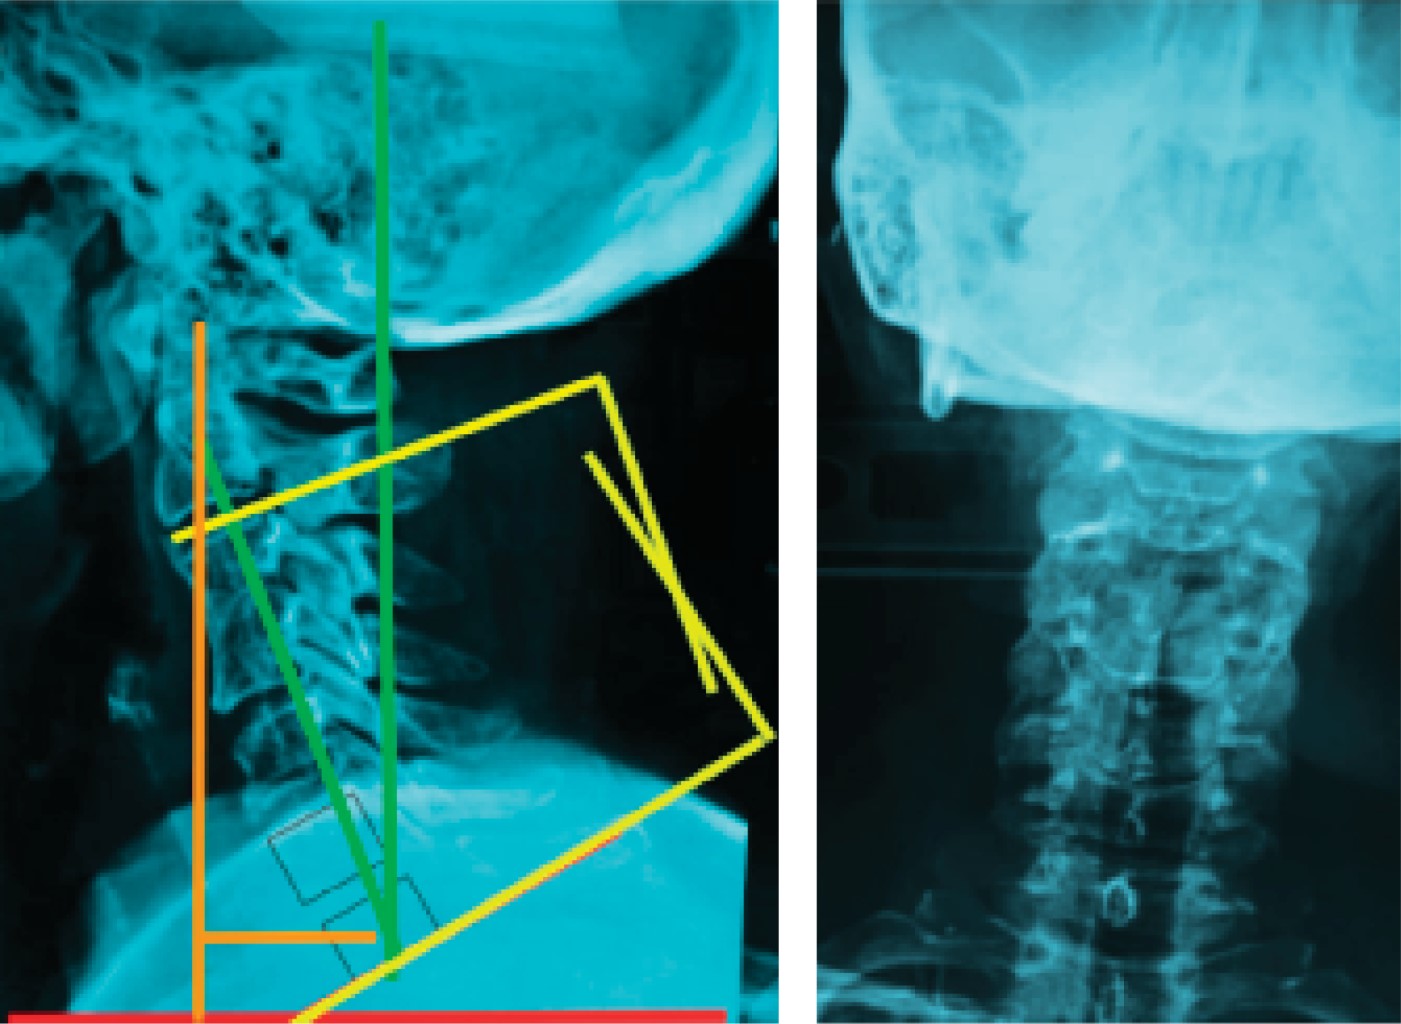

Figure 1